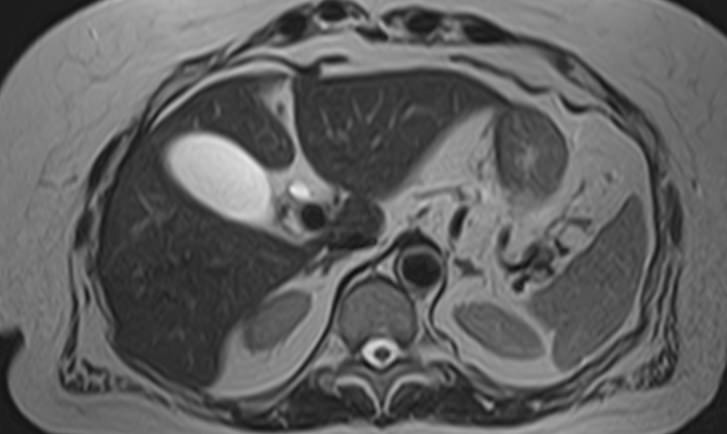

Магнитно-резонансная холангиография – это неинвазивный и безопасный метод исследования, который используется для визуализации желчевыводящих путей, включая внутри- и внепеченочные желчные протоки, панкреатический (Вирсунгов) проток и общий желчный проток (холедох). МРТ позволяет оценить анатомические особенности билиарной системы и определить патологию расположенных рядом структур.

Патология билиарной системы проявляется в виде непроходимости желчных протоков и затруднением оттока желчи. Нарушение отделения желчи может быть вызвано наличием камней, развитием объемного образования внутри протока или сдавлением протока опухолью извне.

С помощью магнитно-резонансной холангиографии можно выявить следующие патологии:

- Закупорка протоков конкрементами;

- Доброкачественные и злокачественные опухоли внутри просвета протоков или новообразования, исходящие из окружающих тканей;